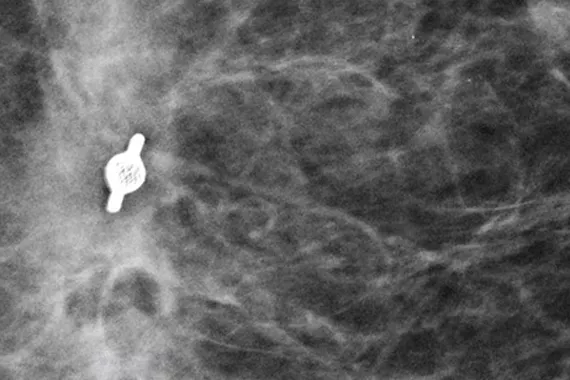

Image Gallery